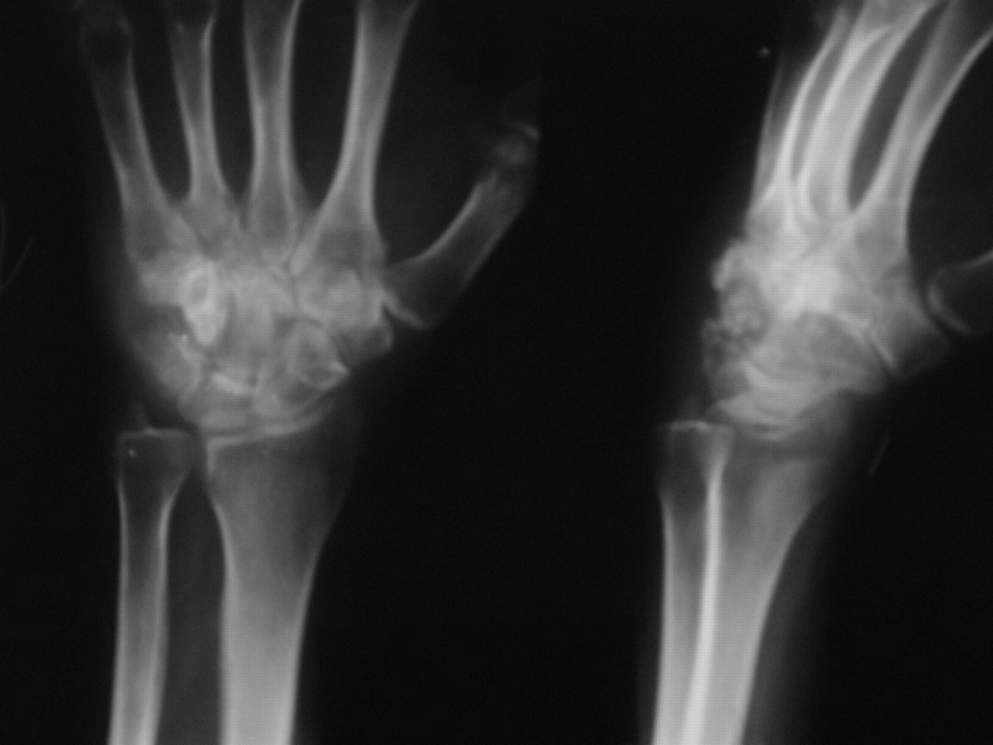

Уважаемые коллеги,на лечении больная 30 лет,с непонятным деструктивным

процессом в левой кисти

Из анамнеза:около 1,5лет назад  смутно отмечает травму левой кисти

(ударилась тылом левой кисти),значения не придала,за медицинской помощью

не обращалась.Боли не беспокоили.После травмы -беременность,нормальные

роды.За месяц до родов больную стали беспокоить боли в области левого

кистевого сустава,ограничение движений в кистевом суставе.В мае 2007г

при осмотре-стойкая контрактура кистевого сустава в положении умеренной

ладонной флексии.Гиперестезия кожных покровов тыла

кисти,лёгкое,преходящее онемение пальцев левой кисти.Пальпация кистевого

сустава резко болезнена.На рентгенограммах(прилагаются)очаг деструкции в

области крючковидной кости с свободно лежащим фрагментом костной плотности.